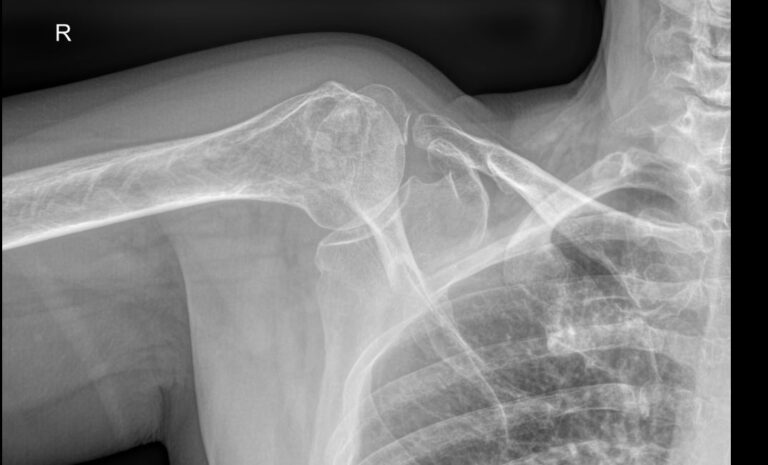

Плечевой сустав ― крупное сочленение, соединяющее верхнюю конечность с телом. По строению он считается простым за счет всего двух суставных поверхностей, для него доступны движения во многих направлениях, что обеспечивает большую свободу для действий рукой. Соответственно, и травма суставу может быть нанесена с разных сторон: при ударе, падении на руку, дергании за нее или резком поднятии большого веса. Кроме вывихов и переломов сустав подвержен системным заболеваниям, типичным для суставов.

Рентгенография относится к стандартным методам диагностики плечевых суставов. На снимке можно обнаружить все патологические изменения, произошедшие в данной области, а также стадии болезни. Рентген используется также для выбора метода лечения и его контроля. Рентгеновское оборудование последнего поколения позволяет делать серию снимков с минимальной дозой облучения. Это важно, так как дает возможность выполнить необходимое количество снимков в динамике.

Снимки выполняются в разных проекциях, в зависимости от того, какой элемент сустава требуется визуализировать.